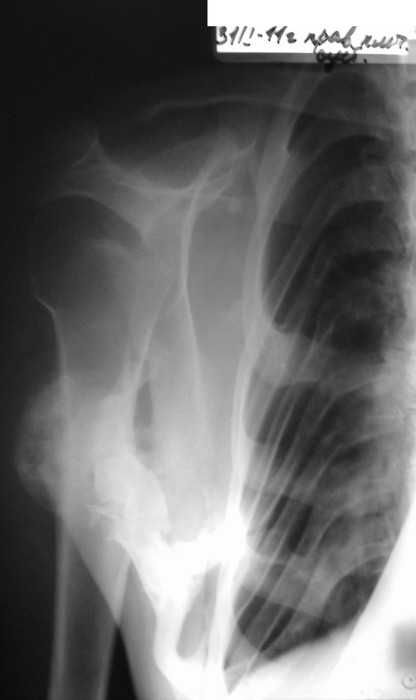

Re: Врожденная аномалия, множественные экзостозы

рентгенограммы